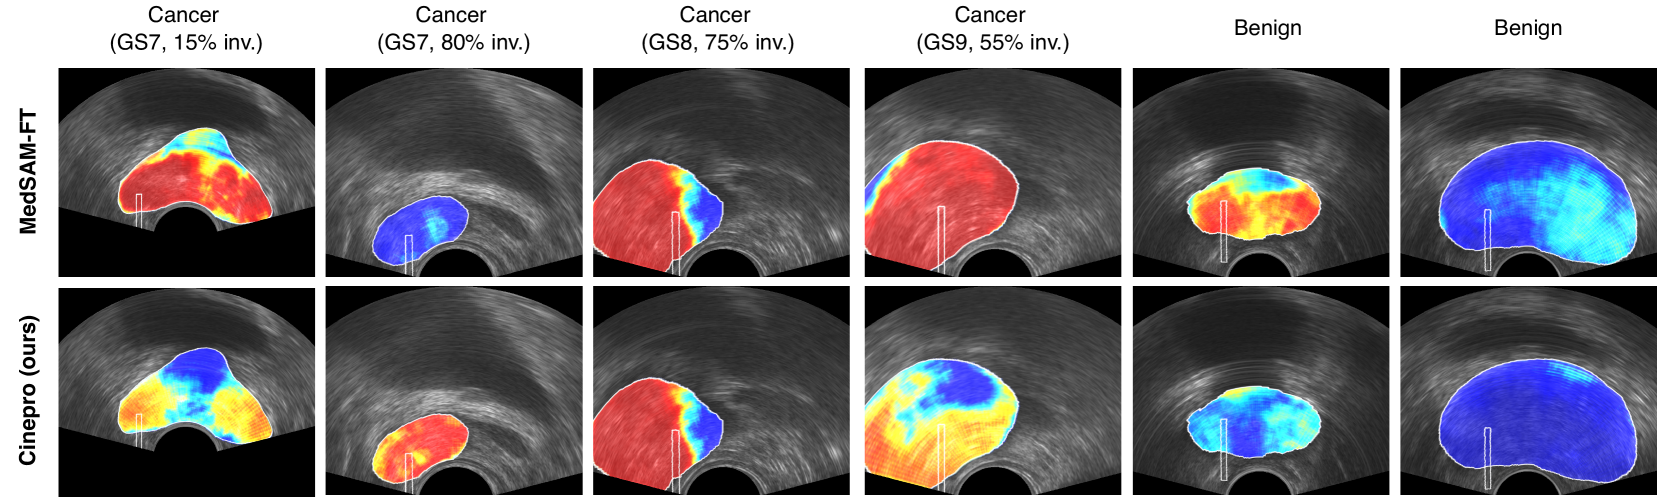

Refer to caption

Fig. 2: Qualitative comparison of Cinepro with our finetuned MedSAM baseline.

Qualitative results: Figure 2 shows prediction heatmaps using both Cinepro and the fine-tuned MedSAM approaches described earlier. We show four cancer examples with different Gleason scores and cancer involvement, and 2 benign examples. We observe that the activations of the output masks generated by Cinepro are less strong in low-involvement cores, thus providing a more accurate form of tissue characterization that matches the involvement, than the baseline. This is especially true for involvement values in the range of 15-70%, with Cinepro producing average predictions that are close to the true distribution of cancer. For high involvement cores, both methods are comparable and perform well, but Cinepro outperforms fine-tuned MedSAM by achieving a higher true positive rate. Finally, the performance of the two models on benign cores is also comparable, but MedSAM produces more false positives in the needle region.